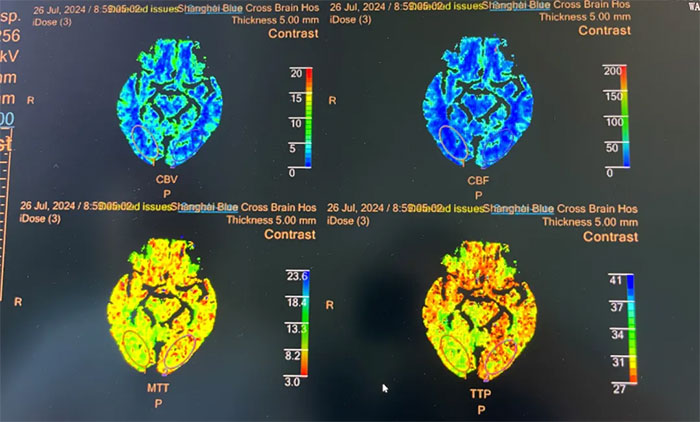

头颅MRI+SWI+DTI提示脑干梗塞,双侧桥臂变性;双侧放射冠区、额顶叶散在腔梗、缺血灶。基底动脉HRMR平扫+增强提示基底动脉管壁增厚伴重度狭窄。头颅CTP显示,右侧顶枕颞叶局部脑组织灌注较对侧稍减低。DSA提示基底动脉中段重度狭窄。

▲ 头颅CTP显示右侧顶枕颞叶局部脑组织灌注较对侧稍减低